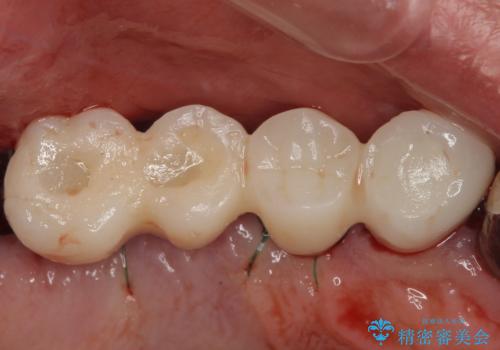

インプラントが無事に生着した後に、オールセラミッククラウンにて補綴治療を行うこととしました。

後方2本を先に埋入し、即日で仮歯を装着しましたが、徐々にインプラントが骨内で緩んでしまい、手前のインプラント埋入時に再埋入することとなりました。

再埋入後は緩くなることもなく、無事に補綴治療を行うことができました。